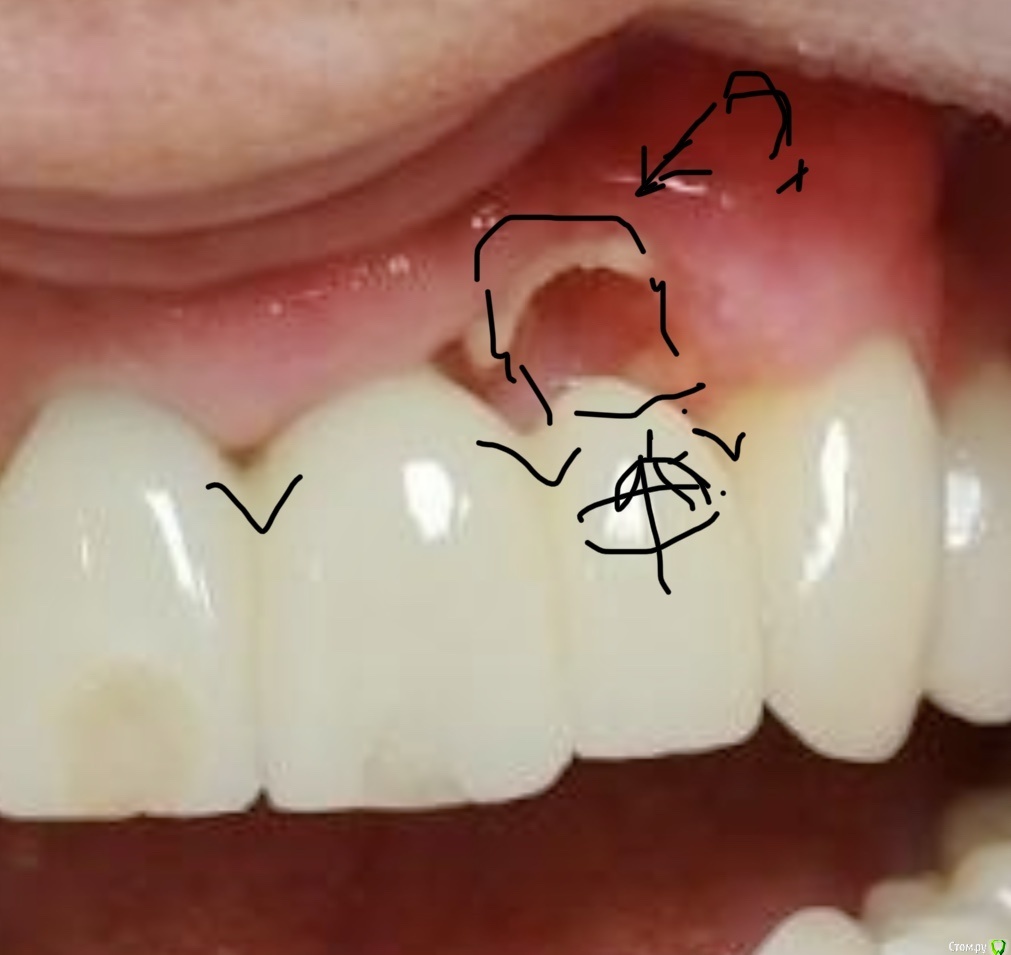

maksimstom Опубликовано 27 октября, 2020 Поделиться Опубликовано 27 октября, 2020 Добрый день, коллеги. Подскажите как бы поступили. 1,5 мес назад удалены зубы 1.2-2.2, установлены импл 11,21, сст вестибулярного 1.2-2.2. Фото до и после прилагаются(рг фото при необходимости добавлю, на работе осталось) в плане 1,5мес ждать пока заживет десна , далее что-то думать, склоняюсь к Сузуки, мб несколько этапов. Ссылка на комментарий

колесников Опубликовано 27 октября, 2020 Поделиться Опубликовано 27 октября, 2020 Здравствуйте! Во первых что это за фрагмент белеет? Во вторых нужно подкорректировать реставрацию и пропилить пространство для сосочков. Далее я бы добавил сст в расщеплённый лоскут ,(разрез с гребня отступя небнее,как бы сместить ткани вестибулярно )и сделать овоид на 22ом. ( Там явно костный дефект -это вершина треугольника. Сосочки 21,23-это основание. Основание будет стремиться к вершине. ) Чере 2 недели после снятия швов применять ирригатор. Оставить созревать на 1,5-2мес. По итогу ,решать о пластике сосочка 21-22 по масана. PS. 11 шахта вестибулярно,надеюсь там есть балкон,иначе десневой контур улетит апекально. Ссылка на комментарий

maksimstom Опубликовано 28 октября, 2020 Автор Поделиться Опубликовано 28 октября, 2020 Белеет кость, во время операции перекрывал ее сст от 23 до 11 с небольшой надеждой на то что запитается) наверно отвалится скоро. Положение импл из-за анатомии гребня, балкон есть. Спасибо за совет, наверно так и поступлю, но думаю подождать все-таки месяц пусть десна созреет Ссылка на комментарий

колесников Опубликовано 28 октября, 2020 Поделиться Опубликовано 28 октября, 2020 Белеет кость, во время операции перекрывал ее сст от 23 до 11 с небольшой надеждой на то что запитается) наверно отвалится скоро. Положение импл из-за анатомии гребня, балкон есть. Спасибо за совет, наверно так и поступлю, но думаю подождать все-таки месяц пусть десна созреет даже не знаю что сказать. Эстетический прогноз серьезный. Оголенный фрагмент секвестрируется 1 Ссылка на комментарий

Дмитрий М Опубликовано 29 октября, 2020 Поделиться Опубликовано 29 октября, 2020 (изменено) я бы скусил фрагмент оголенной кости, ждать более глубокого инфицирования нет смыслаи проводить повторную пластику как предложил колесников думаю подождать все-таки месяц пусть десна созреет1,5 мес уже прошло, в этом месте уже ничего не созреет, трансплантат отвалился Изменено 29 октября, 2020 пользователем Дмитрий М Ссылка на комментарий